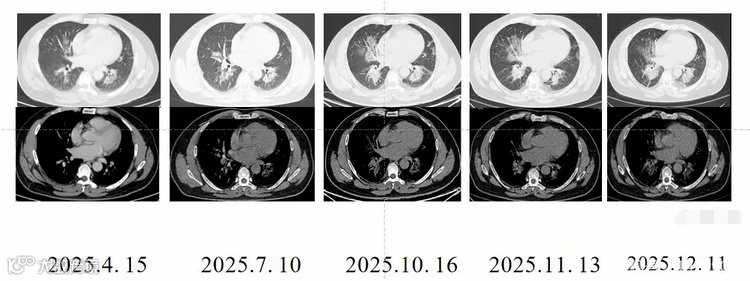

去年四月,装修工老王感冒后出现了胸闷、咳嗽、咳痰的症状,去当地医院就诊。检查显示其双肺有渗出性病变,无法排除肿瘤、肺炎的可能,随即转往了河南省人民医院。河南省人民医院经过系统检查,发现老王体内有肺炎链球菌等病菌,对症抗感染治疗后,胸闷症状仍未缓解,病因成谜。就在医生准备进一步排查时,老王坚持要出院。医生建议老王每隔一两个月复诊一次,但老王并不当回事儿,一拖就是八个多月。期间,河南省人民医院老年医学科主治医师刘雪亚反复提醒老王尽快住院,继续治疗。但老王一直不在意,直到最近胸闷明显加重,他才再次来到医院就诊。经CT引导下肺穿刺活检,医生最终确诊老王患的是罕见病——肺泡蛋白沉积症。

刘雪亚介绍说,肺泡蛋白沉积症就像“肺泡里灌了牛奶糊”一样,是由先天性或继发性因素引起肺表面活性物清除障碍或产生异常,导致大量脂蛋白沉积在肺泡腔和肺泡巨噬细胞的一种罕见呼吸病。该病年发病率约0.36/10万,极为罕见,并且近1/3患者早期无任何症状,容易导致误诊或漏诊。确诊后,老王才知道这种病治疗难度大,极端情况下甚至需要肺移植!万幸的是他的病情还没发展到该阶段。医生采用雾化联合全肺灌洗术的治疗方案,用了三个多小时,才把老王肺泡里的“牛奶糊”样物质清理干净,目前老王正在康复中。